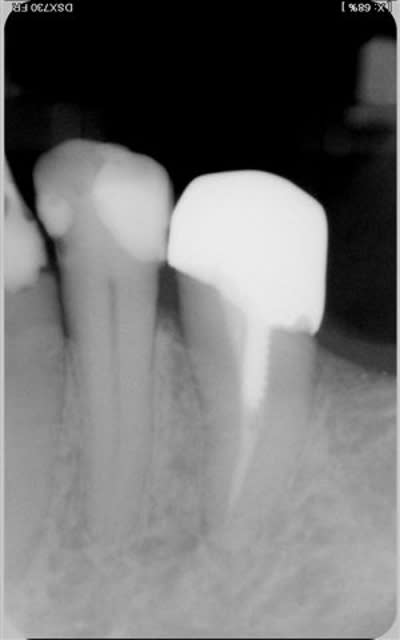

Noa:un cas où je n'ai mme pas fait de paro(et j'aurais dû et je vais la rappeler d'ailleurs)

pr le moment elle a gagné 3 ans,et un silence clinique

ce n'est pas parfait mais en 2005 la solution implantaire était inenvisageable financièrement et ttes les dents sont presentes sur l'arcade ...

une PBM une dent?

ou la 27 laissée sans antagoniste?

c'est vraiment mieux?

une radio en trop qui ne concerne pas ce cas mais comme déjà dit par je ne sais qui, impossible de l'effacer